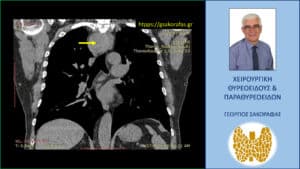

Χαμηλότερη τομή στην αξονική τομογραφία – εμφανής η σε βάθος κατάδυση του δεξιού λοβού στο μεσοθωράκιο (κίτρινο βέλος)

Καταδυόμενη βρογχοκήλη. Αξονική τομογραφία – κατά μέτωπο διατομή. Εμφανής η σε βάθος κατάδυση του δεξιού λοβού στο μεσοθωράκιο (κίτρινο βέλος) που φθάνει σχεδόν στο ύψος του διχασμού της τραχείας, που απωθείται προς τα αριστερά.

Αξονική τομογραφία – κατά μέτωπο διατομή. Εμφανής η σε βάθος κατάδυση του δεξιού λοβού στο μεσοθωράκιο (κίτρινο βέλος) που φθάνει σχεδόν στο ύψος του διχασμού της τραχείας, που απωθείται προς τα αριστερά.